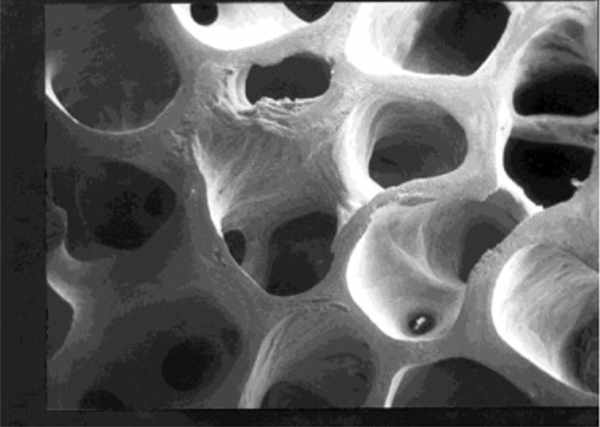

Definition of osteoporosis: A disease characterized by low bone mass and deterioration of bone tissue, which can lead to increased risk of fracture. It is a silent disease until complicated by fractures with minimal or no trauma. Only 50% of people diagnosed with osteoporosis have been tested prior to their fracture – with vertebral (spine) and hip fractures being most common as well as most debilitating, each with significant permanent disability or mortality risk.

Osteoporotic Bone